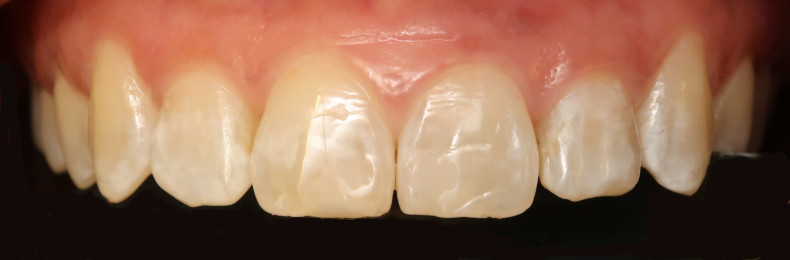

Der intraorale Befund (Abb. 2a–e) sowie die Modellanalyse (Abb. 3a–e) zeigten neben dem Diastema mediale im Oberkiefer vor allen Dingen eine Anteinklination und Supraokklusion beider Fronten. Besonders anterior wiesen beide Zahnbögen eine transversale Enge auf. Dies zeigte sich in einem deutlichen Unterkieferfrontengstand mit Labialkippung des Zahnes 41. Neben Abrasionen und Schlifffacetten, vor allem in der Front, waren auch vereinzelt Gingivarezessionen erkennbar. An Zahn 11 lag eine Schmelzfraktur der Inzisalkante vor. Durch die zwangsgeführte Laterognathie ergab sich eine Mittellinienverschiebung nach rechts von 3 mm. Eine beidseitige Distalokklusion bei vergrößerter sagittaler (6 mm) und vertikaler (5 mm) Stufe war erkennbar. Aufgrund der deutlichen transversalen Zahnbogenenge im Unterkiefer ergab sich links eine Tendenz zum Scherenbiss.